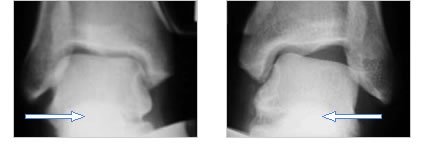

These pictures illustrate a patient with chronic ankle instability. Note how loose the ankle is when it is turned slightly inwards. The ligaments are completely torn in this ankle and the likelihood of recurring sprains is very high.

Here are two X-ray's of a patient with chronic recurrent instability of the ankle. In both the right and the left ankle, an assistant is pushing on the outside of the foot (in the direction of the white arrow) while the XR is taken. The XR on the left is normal, while the one on the right demonstrates a loose (unstable) ankle.